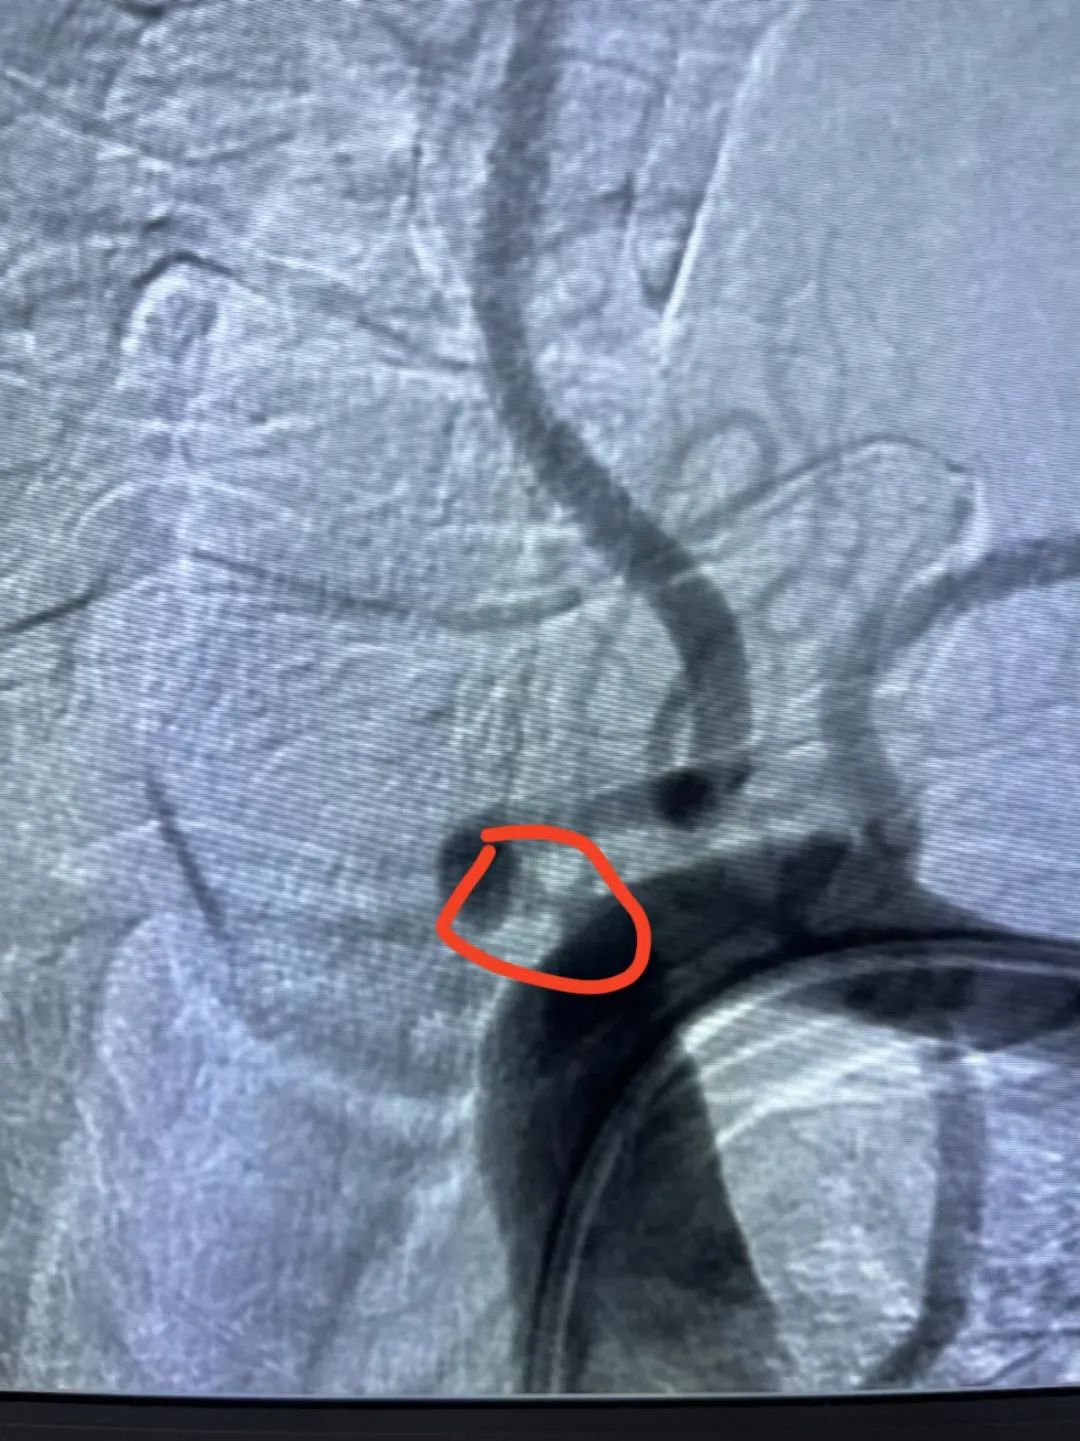

▲狭窄位置

居住在香港的王先生(化名)退休前是一家企业高级管理人员,本该是享受舒适退休生活的时候,1年前却开始感受到走路时有头晕感。尽管他还能保持直线行走,这种不适始终困扰着他。去年7月,他在附近医院进行了一系列检查,但未找出确切的病因,事情便这样被拖到了今年7月。在当地医生的建议下,王先生又做了一次CT血管检查。

椎动脉狭窄是一种脑血管疾病,主要影响颈部两根椎动脉中的一根或两根,导致血流受阻,引起脑部供血不足,从而出现一系列症状。近日,上海德济医院/青岛大学脑科医学中心神经内科汤建军主任就椎动脉狭窄的病因、症状、诊断、治疗等方面进行了科普。

椎动脉狭窄的诊断主要依靠影像学检查,尤其头颈部CT血管成像。

数字减影血管造影:是一种有创检查方法,是诊断椎动脉狭窄的“金标准”。